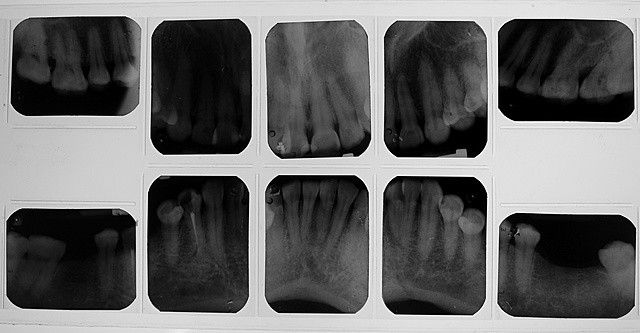

• Análisis radiográfico

Análisis radiográfico

Se tomó serie radiográfica periapical donde se encontró que el OD 4.4 es un diente previamente tratado donde no presenta ninguna lesión periapical y una zona radiopaca en la restauración filtrada de los OD 1.1 y 2.1.